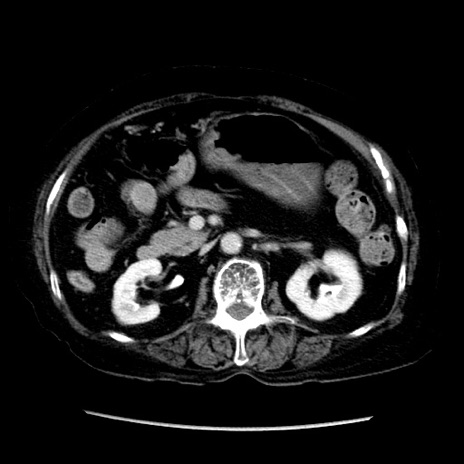

症例14(横断像)

【症例】 90歳代女性

【主訴】 腹痛・嘔吐

【現病歴】今朝から左側腹部痛を認めた。 経過観察していたが、嘔吐を認めたため来院。

【既往歴】 子宮癌術後

【身体所見】 意識清明、BP 127/54mmHg、P 98bpm Sp02 95%(RA)、BT 35.8°C、腹部平坦・軟腸ぜん動音聴取良好、右下腹部圧痛(+) 反跳痛なし

【データ】WBC 9800、CRP 0.46